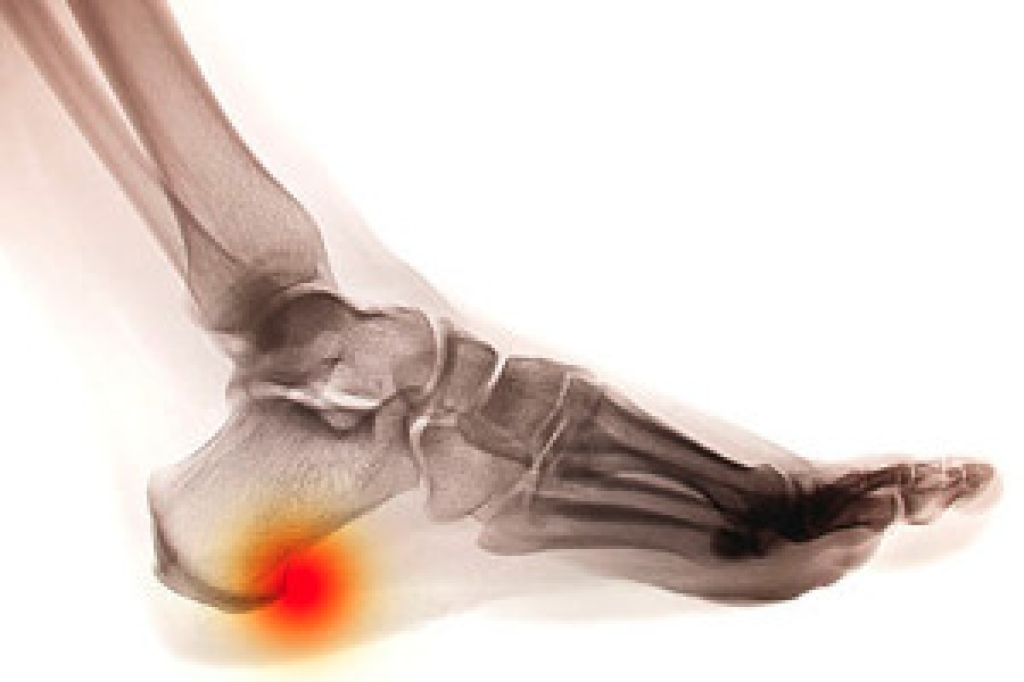

Heel spurs are calcium deposits that develop on the underside of the heel bone, often without causing any discomfort. However, when the plantar fascia ligament, which connects the heel to the toes, undergoes excessive tension or strain, it can become inflamed. This may lead to a condition known as plantar fasciitis, which can cause the heel spur to press into the swollen ligament and cause significant pain. While heel spurs themselves are generally painless, they frequently accompany plantar fasciitis, with about 70 percent of cases showing the presence of a heel spur. Preventative measures include wearing shoes with proper arch support, using heel pads, maintaining a healthy weight, and performing calf stretches before engaging in strenuous activities. A podiatrist can provide a comprehensive treatment plan tailored to your specific needs, which may include custom orthotics, physical therapy, and recommendations for supportive footwear. Surgery may be needed to address severe cases, though it carries risks such as increased pain, nerve damage, and fallen arches. If you are experiencing heel pain, it is suggested that you make an appointment with a podiatrist for an exam and treatment.

Heel spurs are formed by calcium deposits on the back of the foot where the heel is. This can also be caused by small fragments of bone breaking off one section of the foot, attaching onto the back of the foot. Heel spurs can also be bone growth on the back of the foot and may grow in the direction of the arch of the foot.

The pain associated with spurs is often because of weight placed on the feet. When someone is walking, their entire weight is concentrated on the feet. Bone spurs then have the tendency to affect other bones and tissues around the foot. As the pain continues, the feet will become tender and sensitive over time.